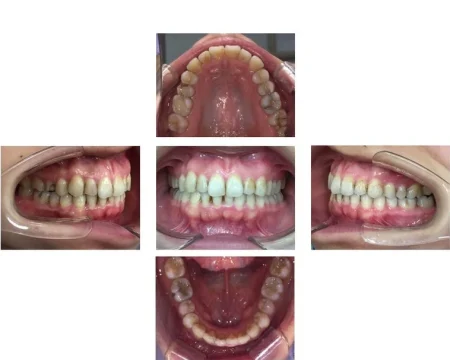

20代女性「オンライン授業中に映る自分の口元が気になる」歯が重なり合ってデコボコしている歯並びをマウスピース型矯正「インビサラインフル」により歯を抜かずきれいに整えた症例

上下前歯が正しい位置に並び、きれいに整いました。

患者様も、以前は笑うときに口元を隠すなど気にしておられましたが、現在は笑顔でお話しされるようになりました。

- 年齢・性別20代女性

- 治療期間の目安1年9ヶ月

治療費総額の目安665,000円